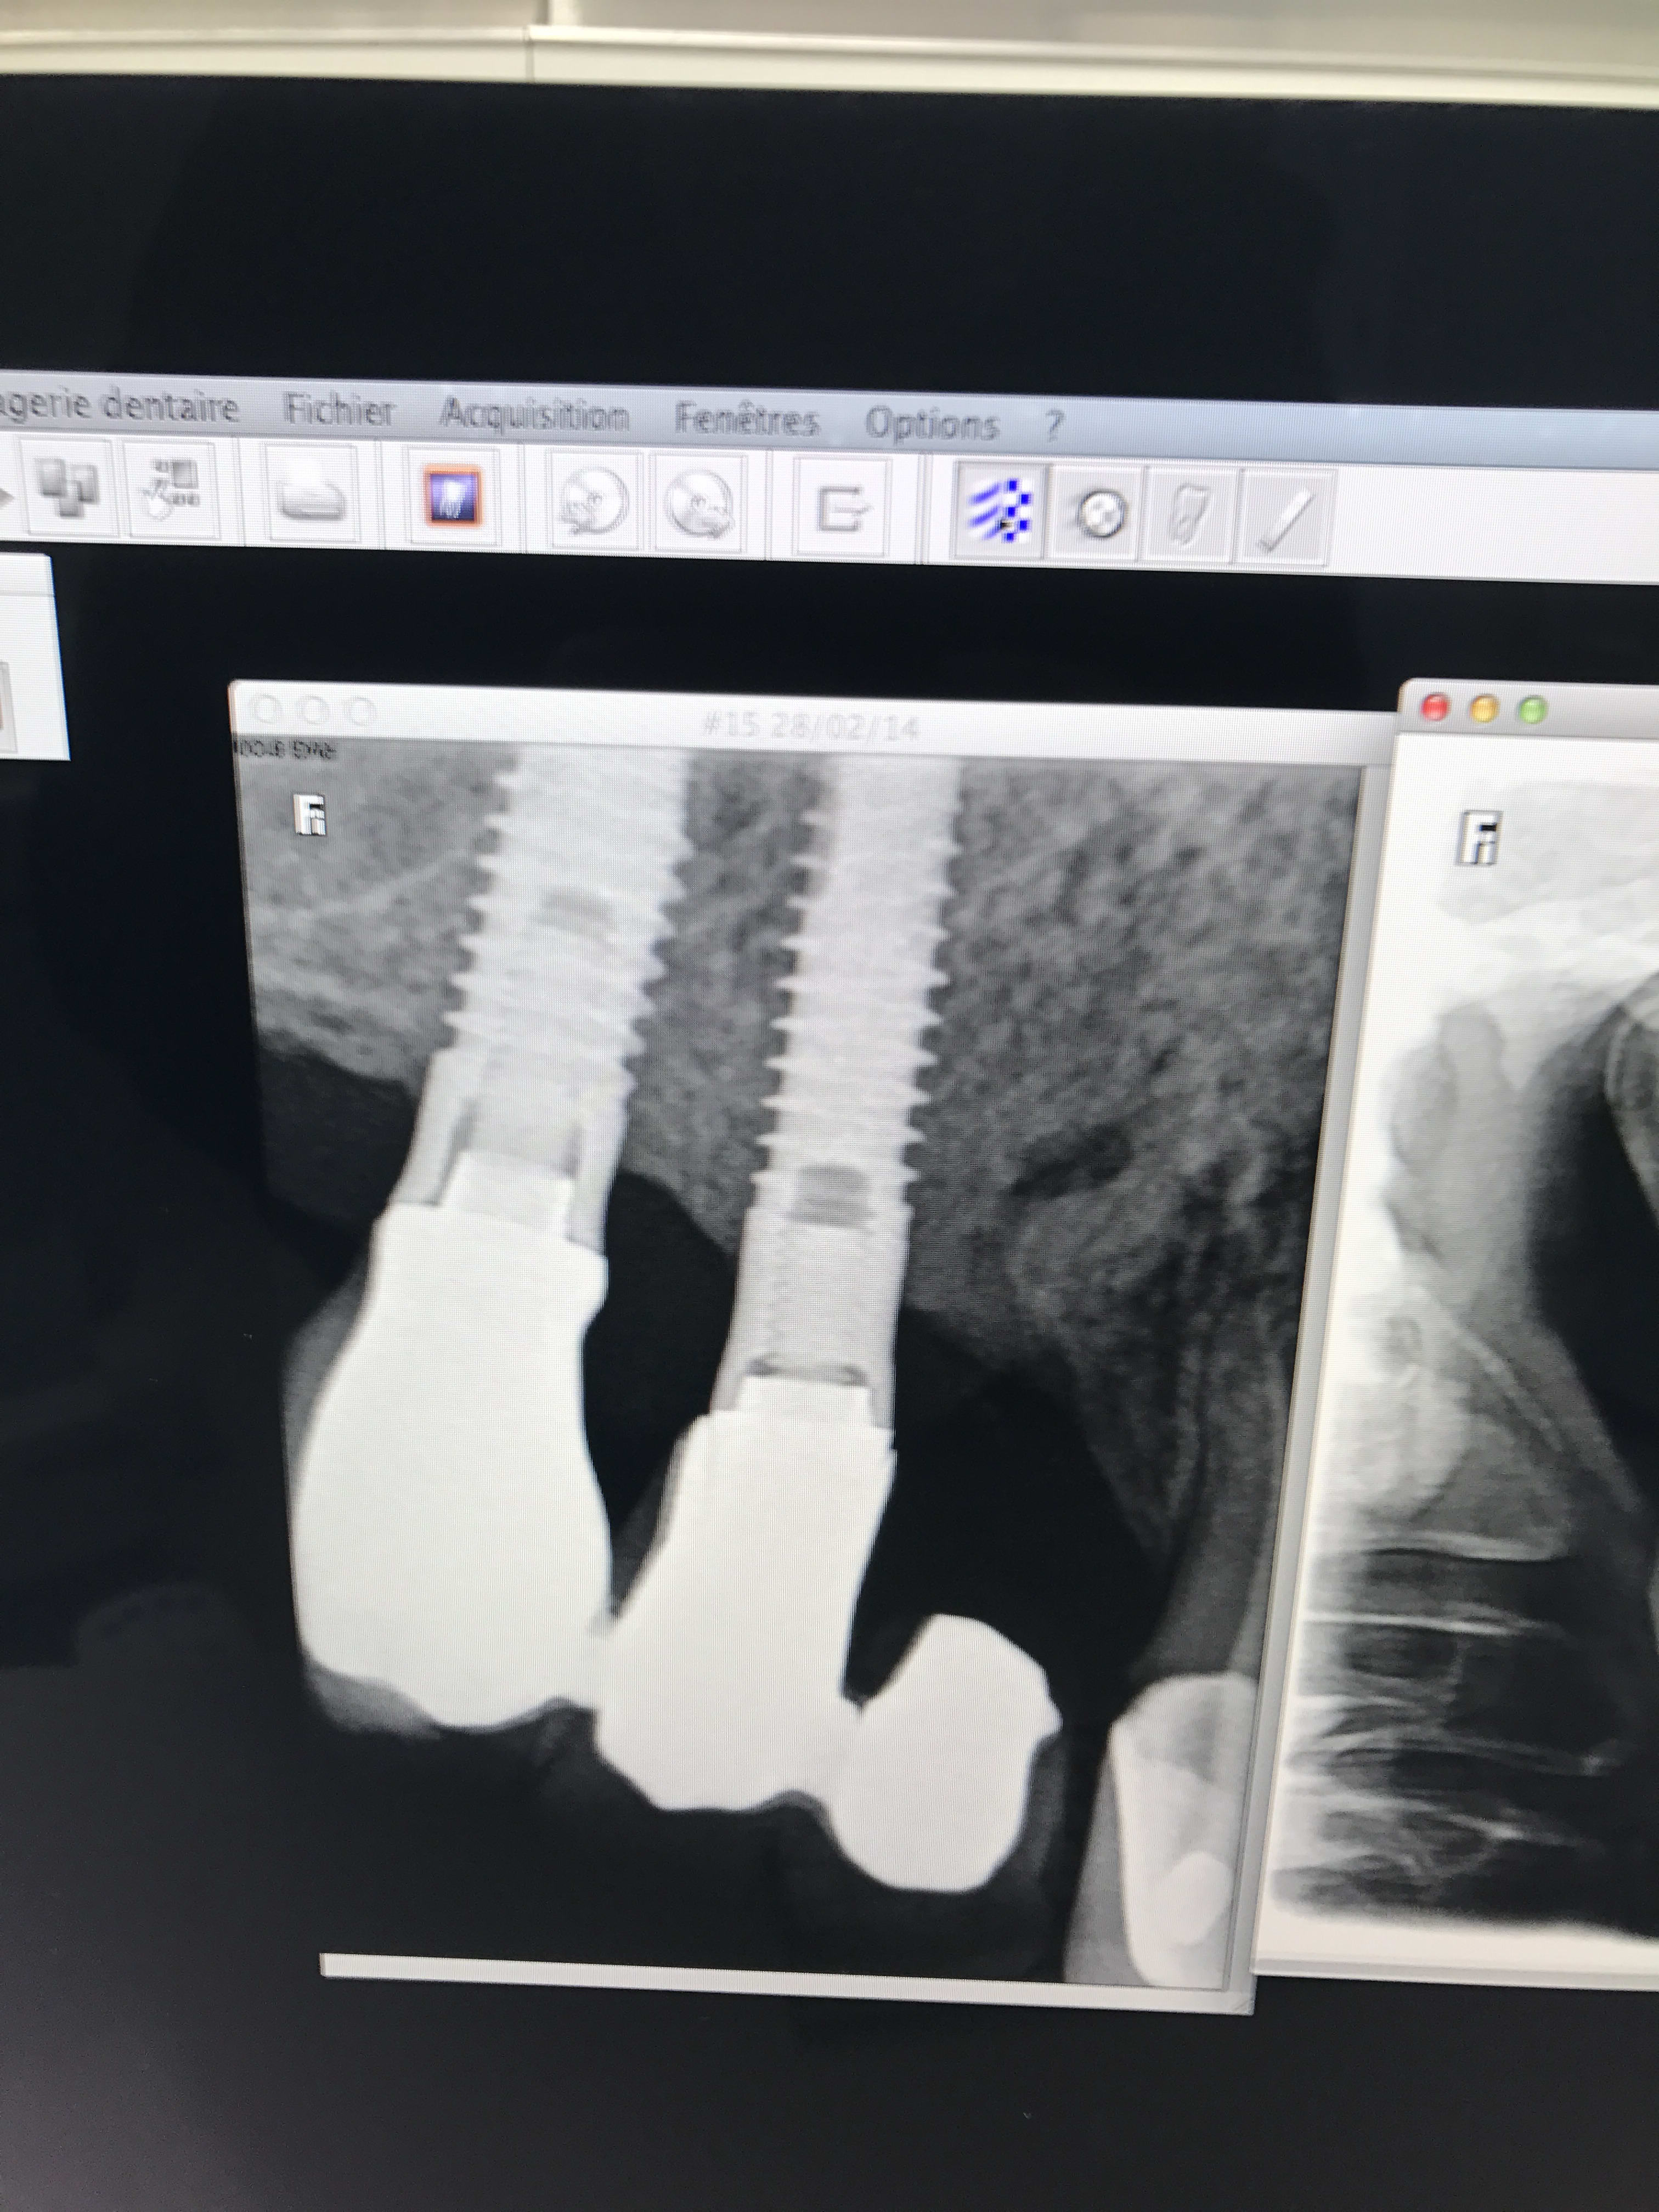

et voila messieurs !

et...heu...tu sais c que c'est comme implant?

parce que si tu veux une identification va falloir faire mieux que des photos merdiques prises au smartphone comme çà!!!

exporte comme il faut tes radios nom de Dieu!!!

Ce sont des Serf... je bosse sur mac et c'est pas évident quand on ne maitrise pas mac pour sortir les radios. J'espère que ça conviendra

serf EVL donc connexion à plat...ce qui veut dire multiunits inutiles si tu n'utilises pas l'hexagone (ce qui est le cas déjà ici si tu étudies bien la rétroalvéolaire)

mais!: l'implant le plus mésial n'est pas dans un axe idéal ce qui veut dire que l'émergence de la vis sera merdique à gérer si tu veux faire de la transvissée...

tu n'as pas d'autre choix que de refaire de la scellée pour ce cas...et petit conseil, utilise des piliers indexés et non pas des piliers sans indexation comme ici...

amha çà c'est dévissé car les piliers n'ont pas étés mis dans la bonne position, ils ont été vissés/serrés de travers...la mastication les a fait revenir dans la bonne position...mais du coup ils ne sont plus serrés...